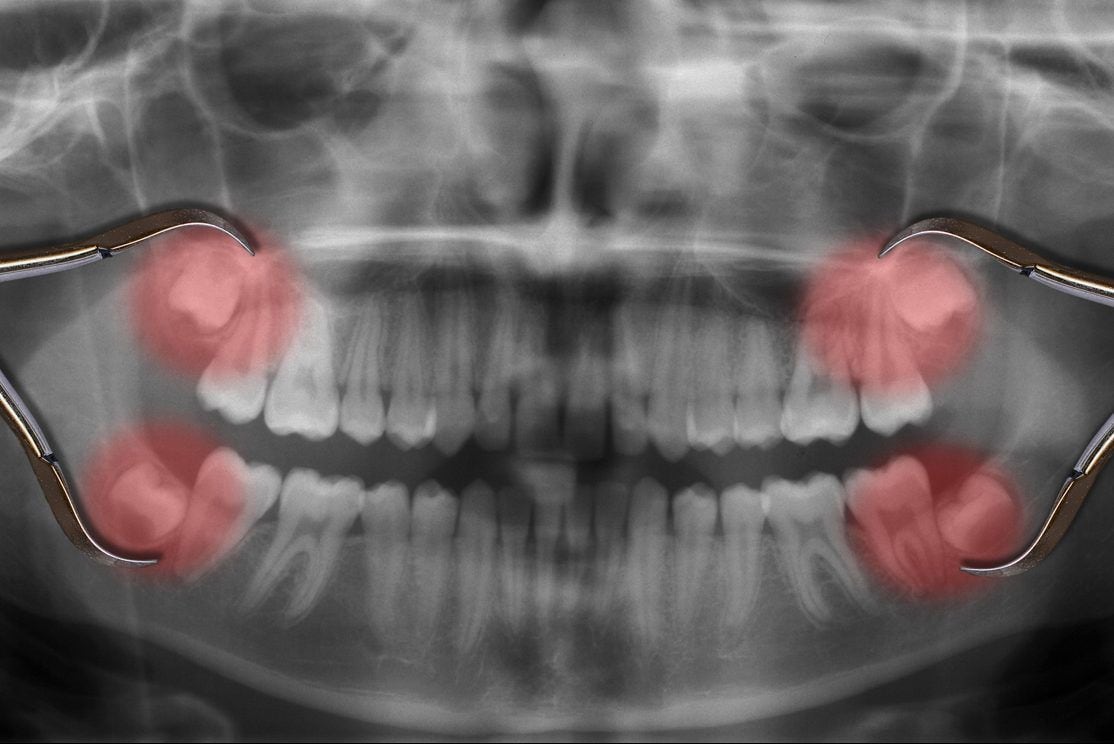

5 Problems Caused By Wisdom Teeth Metro Dental Health Appointments